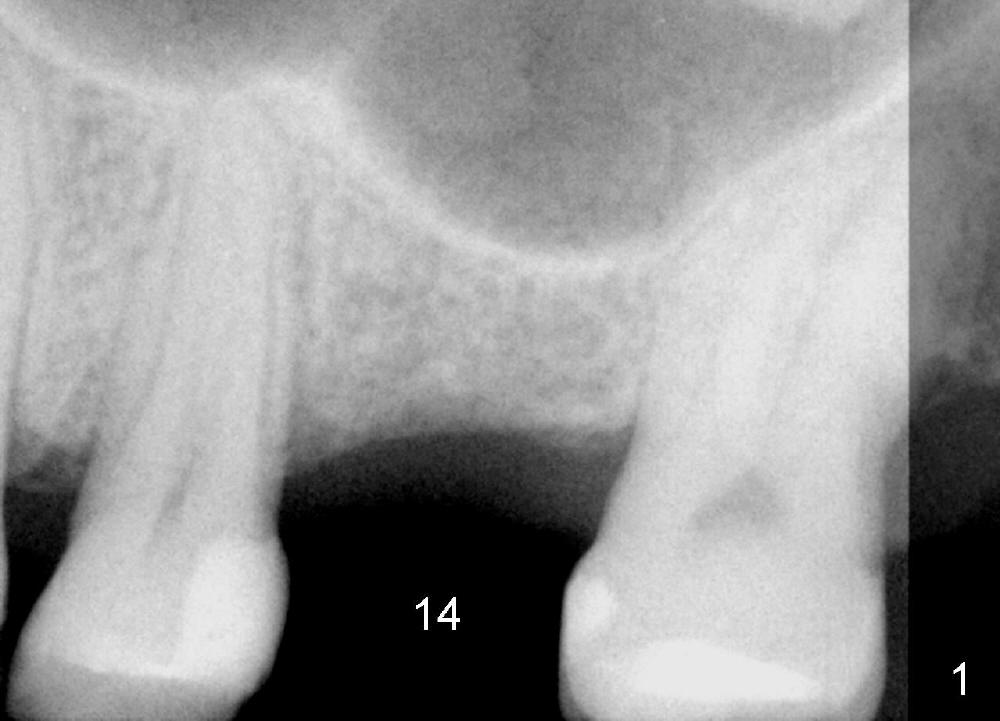

A 48-year-old lady has lost #14 for a while (Fig.1). It looks that bone density at the site of #14 is lower than that mesial to the 2nd premolar. The buccolingual width is wide clinically, although the mesiodistal distance is short (8 mm, Fig.2). A 4-mm tissue punch is used for access. When 1.5 mm pilot drill is used to start osteotomy, it feels that bone density is not low. The first bone expander (2.6 mm) cannot penetrate the bone. Therefore reamers 2.5-3.5 mm are used to increase osteotomy at the depth of 6 mm from the gingival margin. A 4.5x11 mm tap drill is inserted ~ 7 mm with resistance (Fig.3). After 5x11 mm tap, autogenous bone mixed with Osteogen is pushed into the osteotomy and upward. A 5x11 mm implant is placed with > 60 Ncm (Fig.4). After the last X-ray, the implant is torqued 5 more times so that the distal last thread may be able to be fully engaged to the bone. Fig.5 is CT coronal section at the site of #14 5 days postop (B: buccal; L: lingual). Fig.6 is taken 5 months postop with maintenance of sinus lift (*). The crown dislodges 16 months post cementation. In fact the abutment is also loose. The latter is resin bonded, followed by crown cementation (Fig.7). It appears that when the implant is 5 mm or less, the unipost should be permanently cemented in order to prevent crown displacement, particularly for a patient with bruxism and partial edentulism.